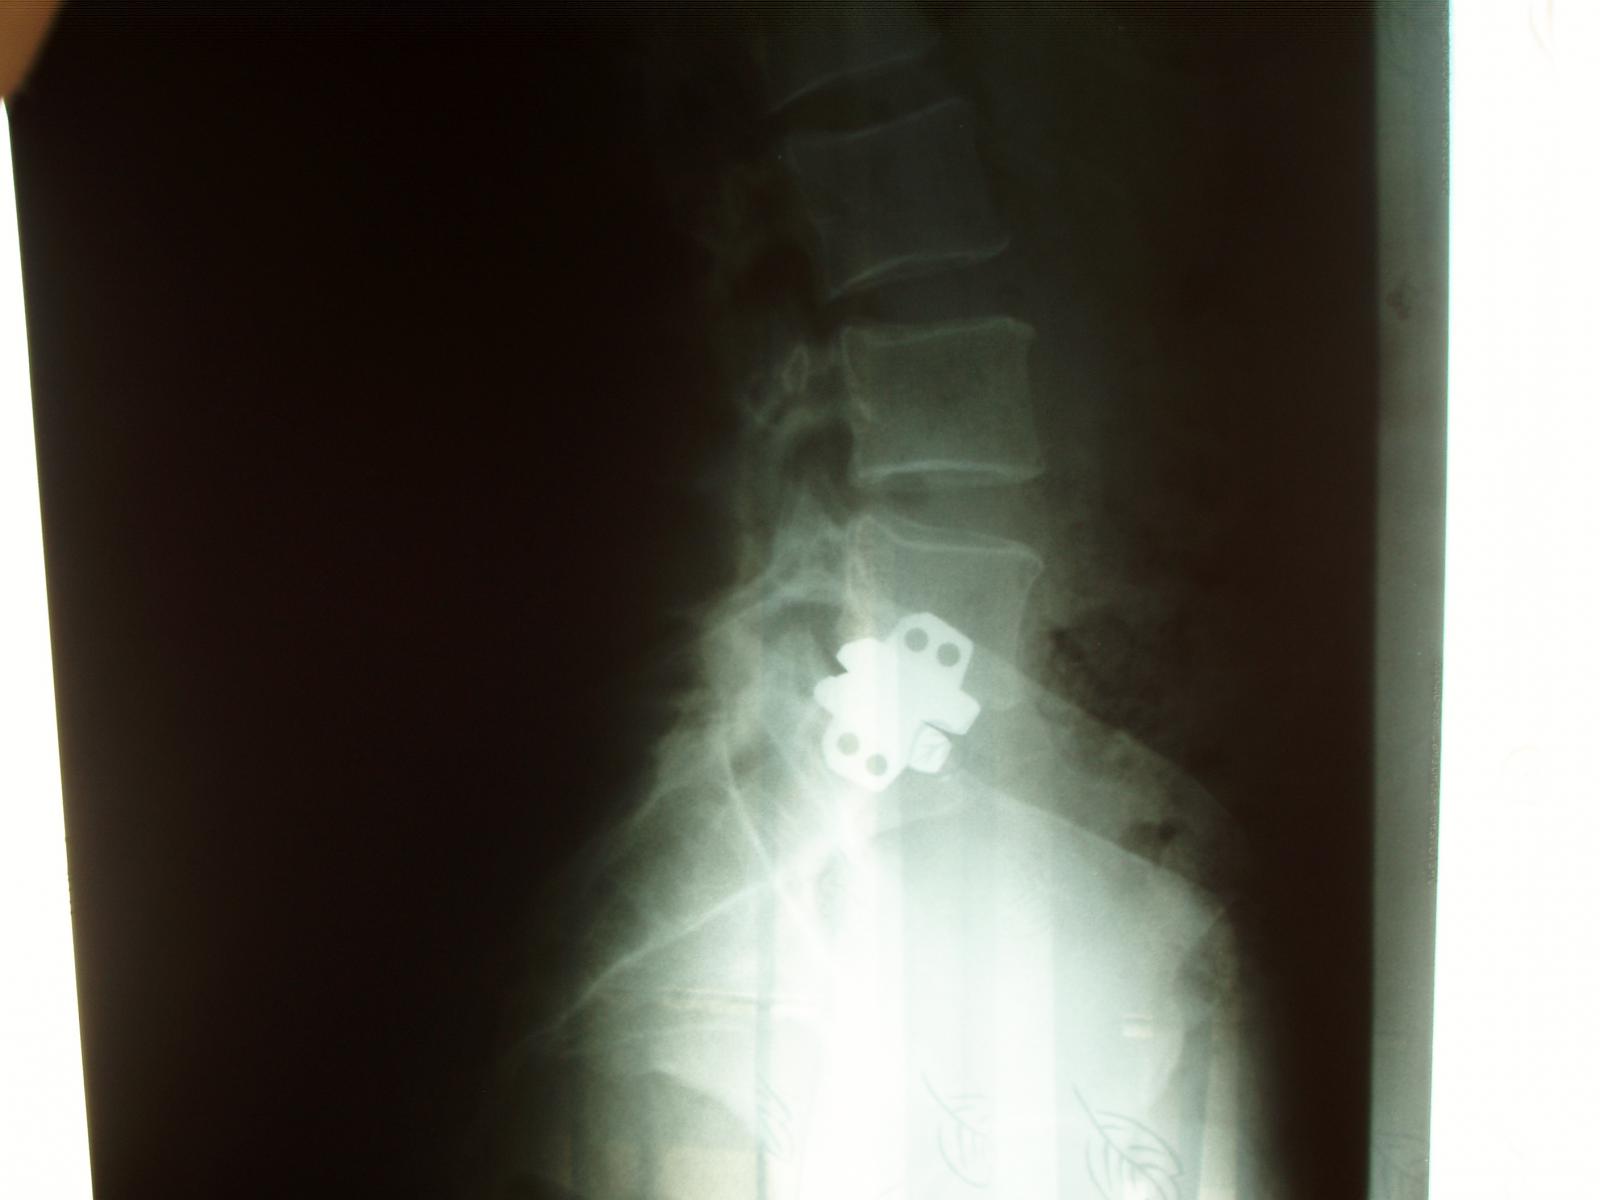

Toto má vchrbtici moja žena. Bola to náročná operácia pred 9rokmi,Tá tvoja je pre lekárov v podstate rutina, budeš určite v pohode.

sanko přiložený následující obrázek:

[71Kb]